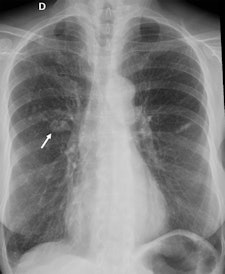

Top: Follow-up imaging of a 72-year-old woman. Preoperative x-ray for skin melanoma. Posteroanterior chest radiography in the upright position shows one suspected pulmonary nodule in the right lung (arrow). Bottom: Digital tomosynthesis image clarifies that the same opacity corresponds to a focal sclerosis within the poster arch of a right rib (arrow). Readers provided a confidence score of 1.Tomography findings were proven by CT (114 patients), chest x-ray during follow-up (105), or histology (18). The final diagnoses included 77 pulmonary opacities, 26 pulmonary scars, 12 pleural lesions, and 122 pulmonary pseudolesions. Tomosynthesis versus chest x-ray presented a higher (p < 0.05) sensitivity (92% vs 15%), specificity (91% vs 9%), overall accuracy (92% vs 12%), and diagnostic confidence (area under ROC, 0.997 vs 0.619). Mean effective dose of chest x-ray vs tomosynthesis was 0.06 vs 0.107 mSv (p < 0.05).